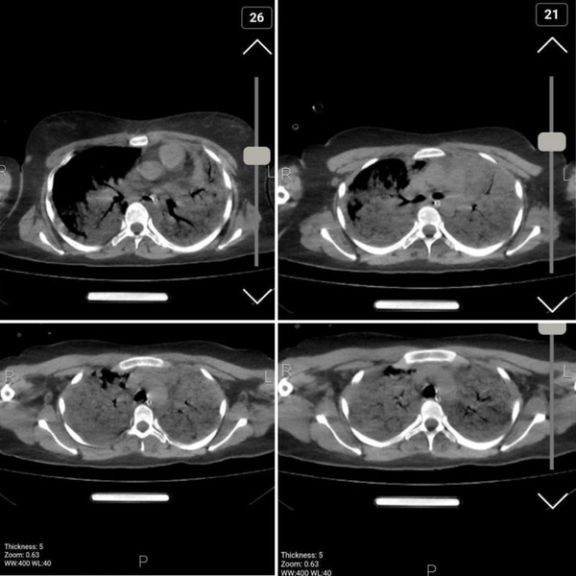

اختصاصی ایراناینترنشنال: سیتیاسکن مهسا نشانگر وجود ترشحات و خون در ریه اوست

تصاویر اختصاصی از سیتیاسکن مهسا امینی که از سوی یک گروه هکری در اختیار ایراناینترنشنال قرار گرفته است نشانگر وجود ترشحات و خون در ریه اوست. به گفته پزشکان، تجمع مایعات در ریه، ناشی از ورود به کما در پی ضربه سنگین به سر اوست